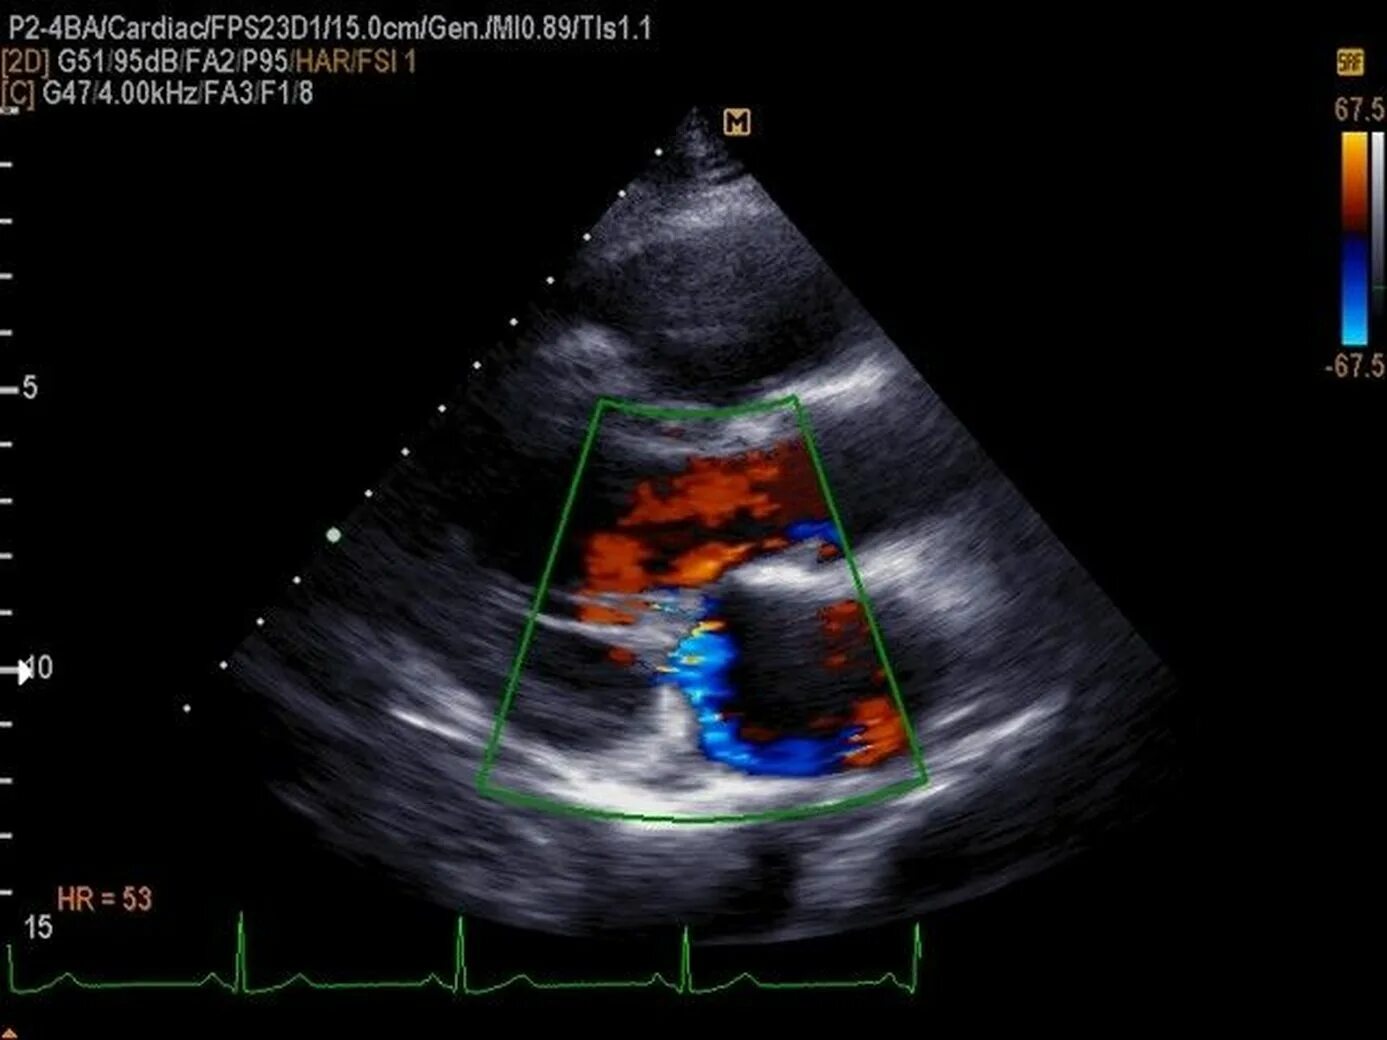

Порок митрального клапана на эхокг. порок митрального клапана на узи. врожденный порок сердца узи. приобретенные пороки сердца в эхокг.

Аортальный стеноз допплер эхокг. митральная недостаточность узи. стеноз аортального клапана эхокардиография. митральный стеноз на узи сердца.

Допплер эхокг расшифровка. створки митрального клапана на эхокг. отрыв хорды трикуспидального клапана на узи. трикуспидальный клапан на эхокг.